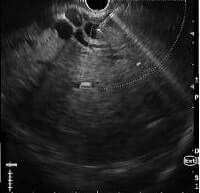

EUS guided biliary access

Diagnosis and treatment: On side viewing endoscopy, large mass lesion seen infiltrating the ampulla and periampullary region was seen. Biopsy from mass lesion revealed poorly differentiated adenocarcinoma. In view of cholangitis, biliary drainage by ERCP (Endoscopic Retrograde Cholangiopancreatography) was tried. However, biliary access was not feasible because of duodenal luminal narrowing and diffuse infiltration. Subsequently, EUS (Endosonography) guided choledochoduodenostomy from first part of duodenum was done and fully covered biliary metallic stent was placed. The procedure was uneventful and patient fever and jaundice subsided. On follow up visit, bilirubin was in normal range, and the patient was planned for chemoradiation due to locally advanced tumor.